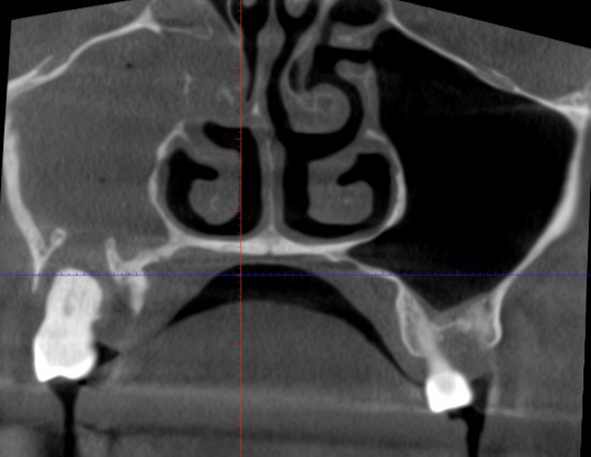

Если вы дочитали до этого места, вы совершенно точно не стоматофоб. Иначе вы испугались бы ещё выше, когда я показал снимок.